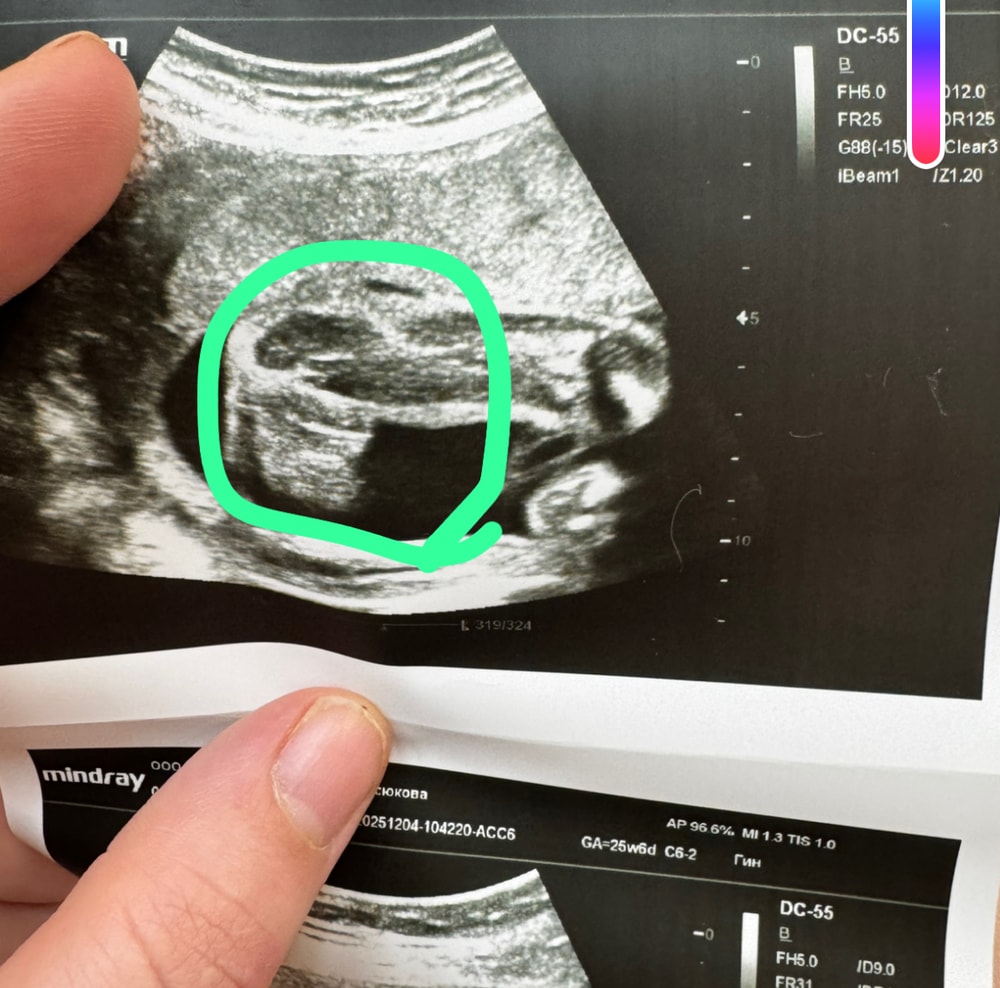

Ну вот решила поделиться, у нас долгожданная дочка 👧

узи показывает, что там девочка 🫢 врач долго смотрела на узи и ребенок лежал удачно - я верю и знаю что там дочка 😍